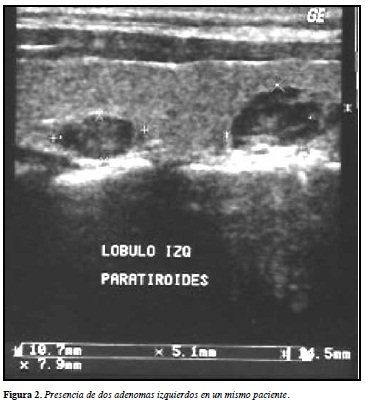

Durante un periodo de dos años se evaluaron en el servicio de radiología del Hospital Santa Sofía (Manizales, Caldas, Colombia, Sur América) pacientes con ERC-5-D (hemodiálisis o diálisis peritoneal), interconsultados por sospecha de hiperparatiroidismo secundario refractario, mayores de 18 años y quienes presentaran valores de PTH intacta mayores a 600 pg/mL, a pesar de recibir terapia con dieta baja en fosfatos, quelantes de fosfatos y vitamina D activa (calcitriol). En todos los pacientes se practicó ultrasonografía de cuello, tiroides- paratiroides con equipo de alta resolución (Equipo Phillips Enviisor CHD - Transductor 12 MHz). De 86 pacientes evaluados se detecto en 30 (34,88%) hiperplasia de glándulas paratiroides (Figuras 1 y 2) (8). En 15 el volumen de las glándulas fue mayor a 500 mm3, con lo cual se consideró que cumplían con los criterios recomendados por la sociedad japonesa en el 2006 para selección de pacientes candidatos a aplicación de etanol percutáneo en hiperparatiroidismo secundario (Tablas 1, 2 y 3) (15). A cada uno de ellos por guía ecográfica y previo consentimiento escrito se les aplicó etanol en cada glándula hiperplásica, siendo el volumen aplicado el de la glándula paratiroides intervenida y calculado según la fórmula: axbxcxjt/6 en mm3, donde a, b y c corresponden al diámetro de las 3 dimensiones de la glándula. Se practicó un máximo de dos aplicaciones por glándula con un intervalo de 30 días (Figura 3). En cada sesión si el número de glándulas fue superior a dos sólo se permitió la infiltración de dos y siempre del mismo lado, continuando a los 30 días con las contralaterales. En el grupo 1 (G1) se incluyeron cinco pacientes con una sola glándula hiperplásica, los grupos 2 (G2), 3 (G3) y 4 (G4) comprendieron tres, dos y cinco pacientes con dos, tres y cuatro glándulas hiperplásicas respectivamente, y se agruparon en el grupo 5 (G5). Los niveles de PTHi se evaluaron a los 30, 60, 90 y 120 días posterior a la ultima aplicación, al igual que las variables calcio, fósforo, producto calcio-fósforo y hemoglobina. La fosfatasa alcalina se evaluó inicialmente y a los tres meses.